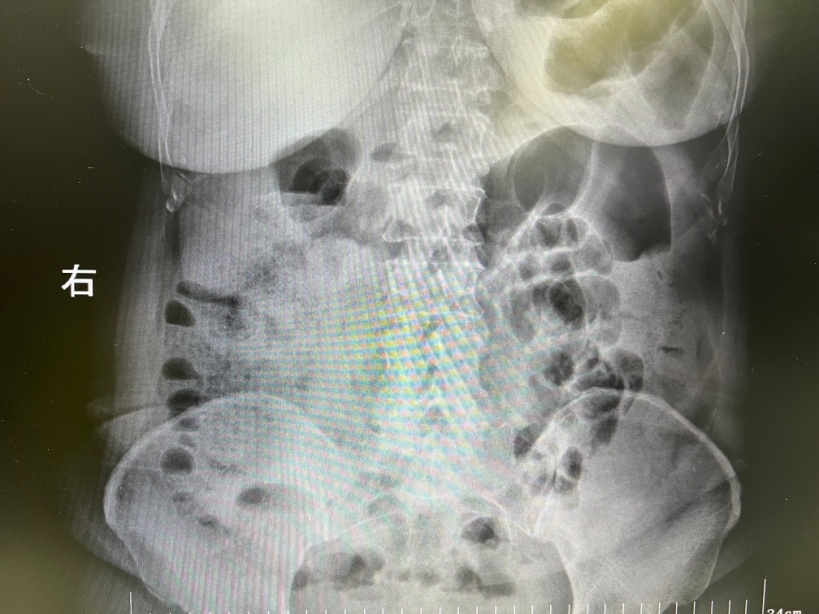

患者院前腹部CT結(jié)果示:腸郁張。